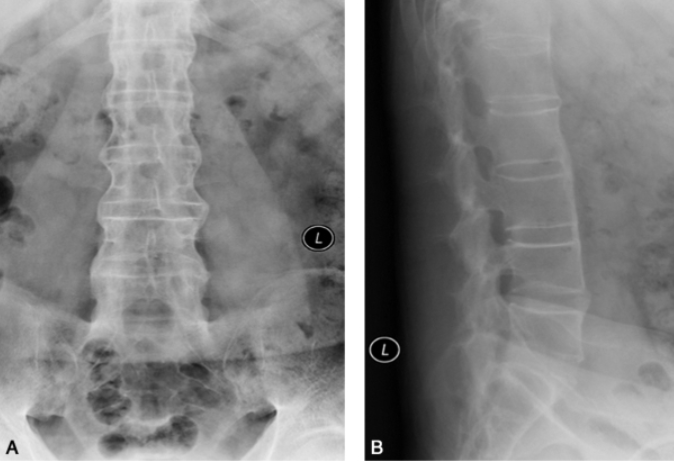

图2 腰椎强直性脊柱炎男,52岁。A、B.腰椎正侧位片显示骶髂关节骨性融合,腰椎体成方椎,椎间小关节面模糊、硬化和增生。

受累在骶髂关节之后,由下脊椎开始,逐渐向上发展。椎体前角表面骨质吸收,导致正常椎体前缘凹陷消失,椎体变成方形呈所谓的“方椎”,椎间小关节面模糊、硬化和增生。骨质可有明显疏松。3%~28%的患者有脊椎间隙变窄和邻间盘椎体骨质破坏、周围多伴有骨质硬化。椎间纤维环、椎间小关节囊、前纵韧带、后纵韧带、黄韧带、棘上韧带和棘间韧带可发生不同程度骨化。椎间纤维环外层骨化,使椎体彼此相连,正位像脊柱呈竹节状。棘间韧带、棘上韧带和两侧椎间小关节囊骨化,形成三条致密纵带,颇具特征(图2)。晚期,脊柱变直,均匀后突或合并侧弯畸形。少数颈椎受累出现寰枢关节半脱位并在半脱位基础上发生融合,合并蛛网膜囊肿者可有腰骶部椎管扩大。